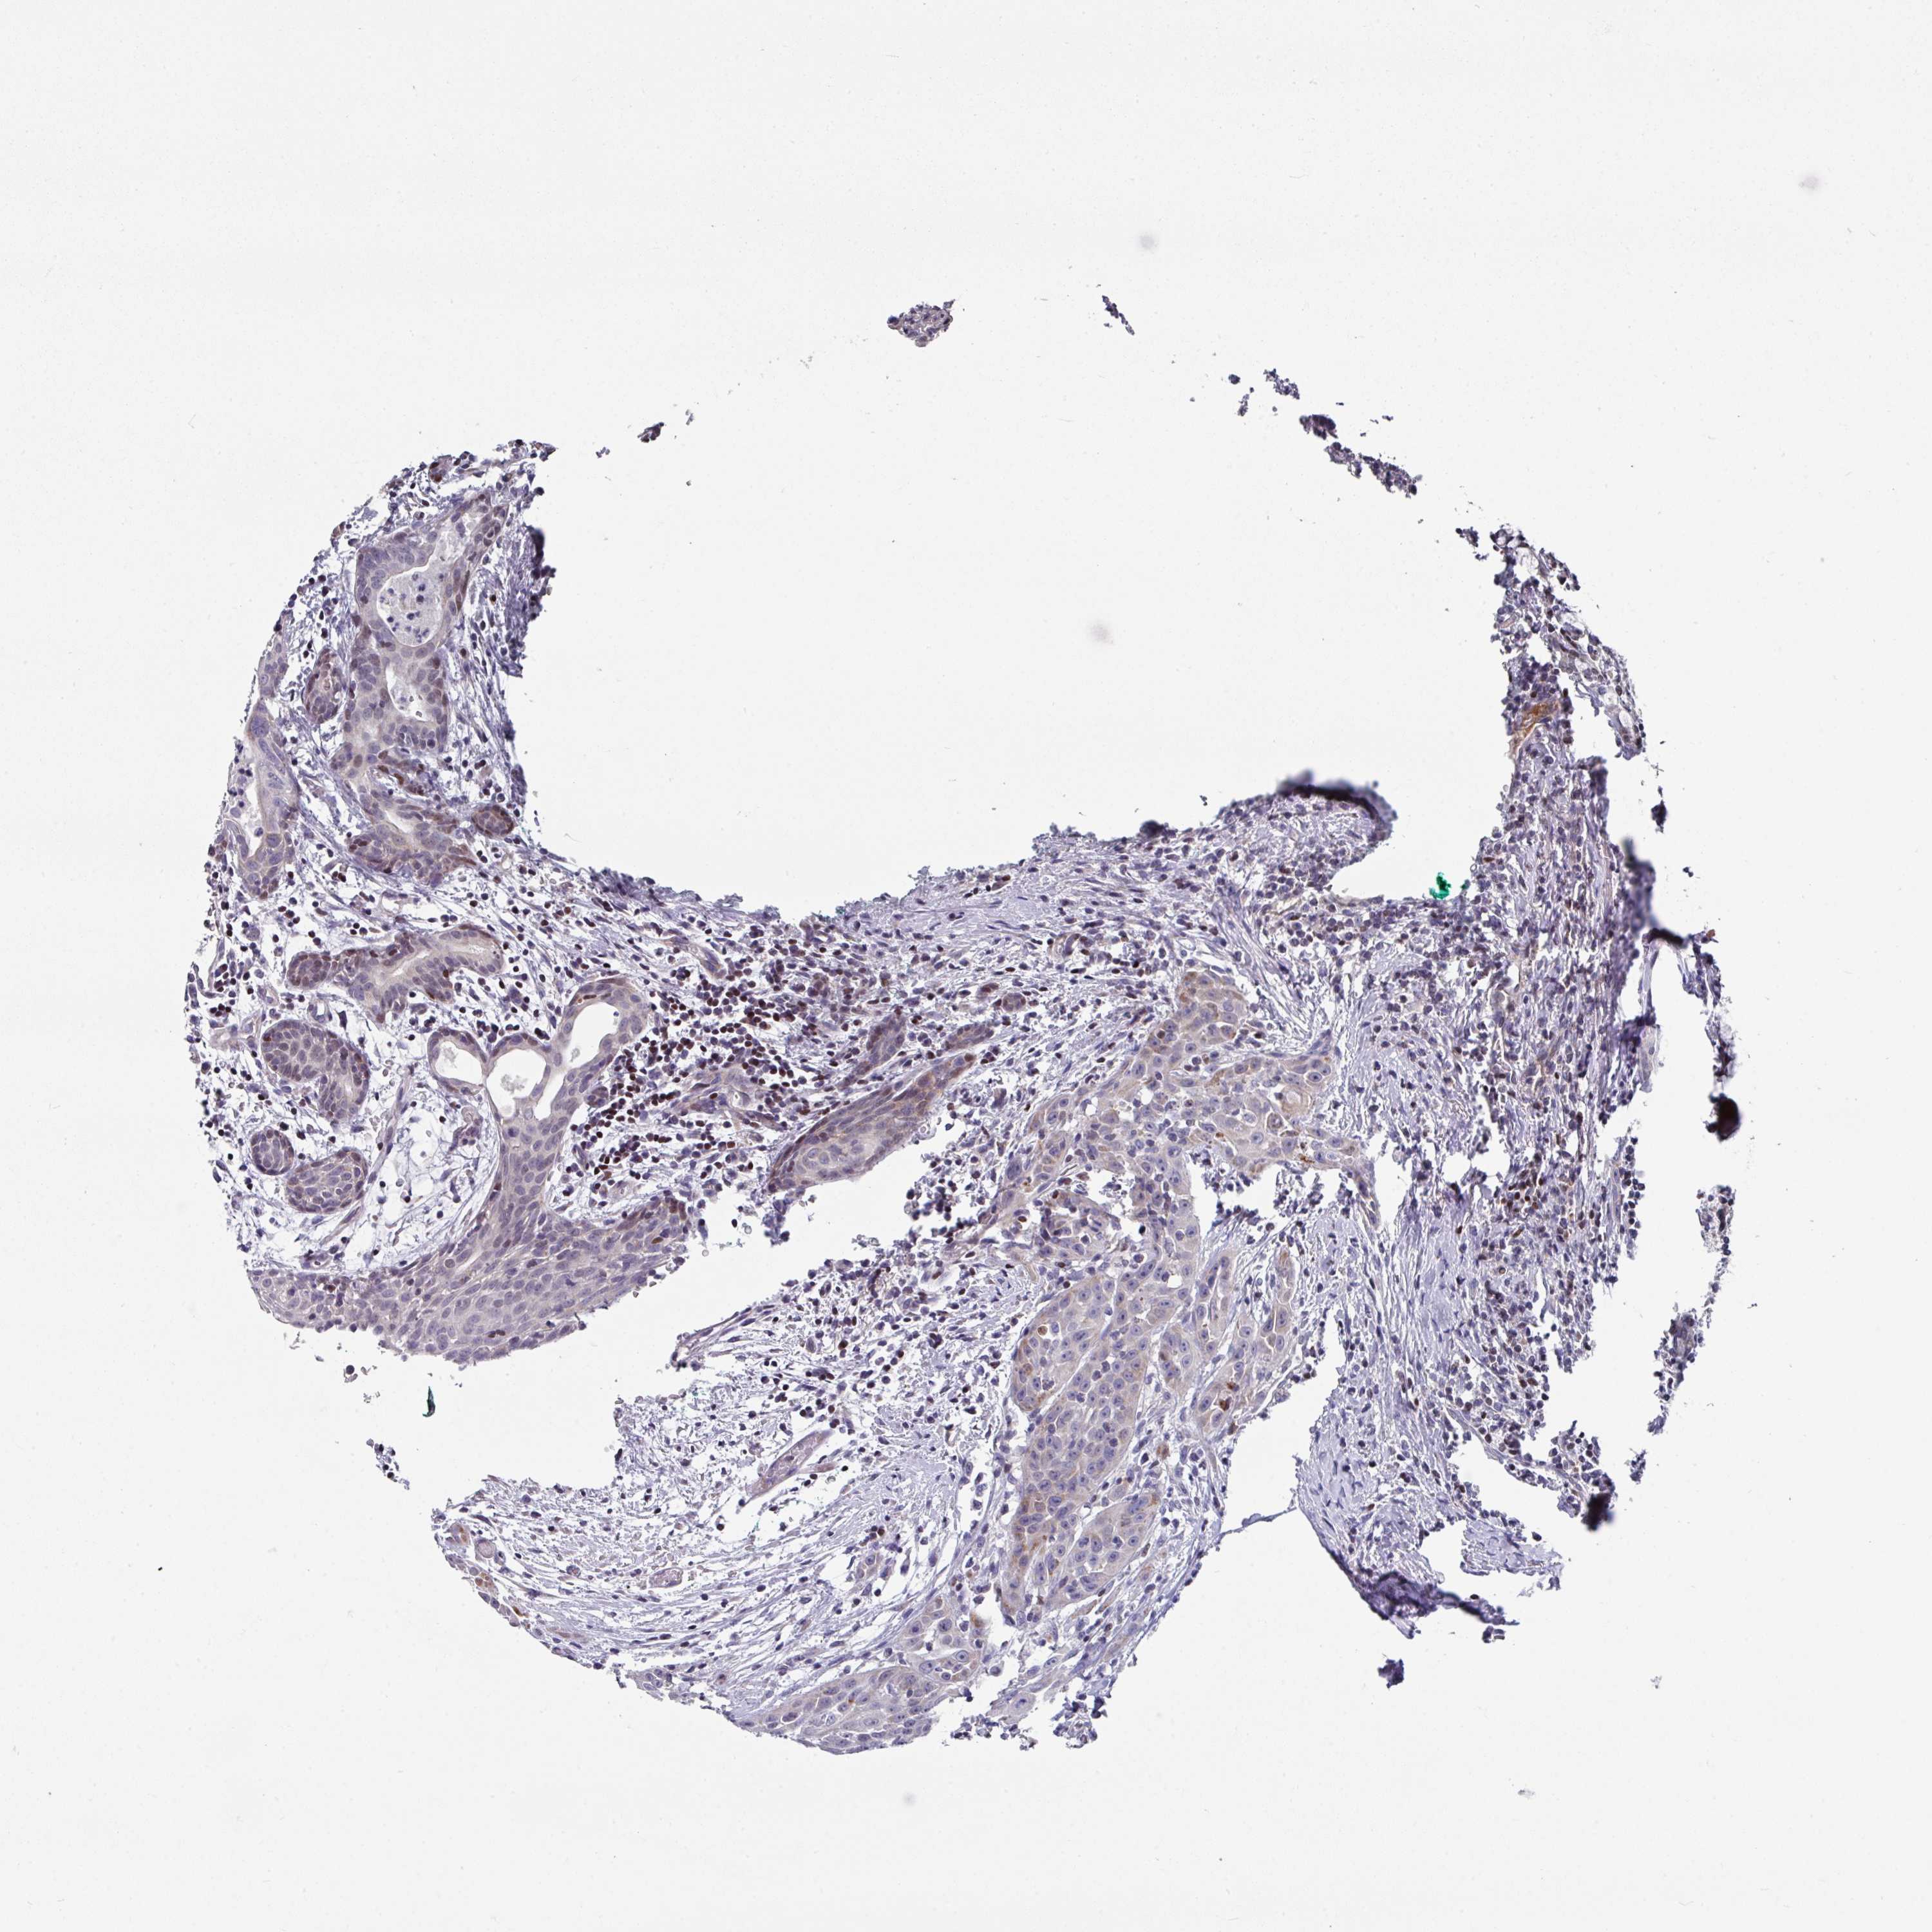

HEAD AND NECK CANCER - Protein expressioni

A mouse-over function shows sample information and annotation data. Click on an image to view it in a full screen mode. Samples can be filtered based on level of antibody staining by selecting one or several of the following categories: high, medium, low and not detected. The assay and annotation is described here.

Antibody stainingi

Antibody staining in the annotated cell types in the current human tissue is reported as not detected, low, medium, or high, based on conventional immunohistochemistry profiling in selected tissues. This score is based on the combination of the staining intensity and fraction of stained cells.

Each image is clickable and will lead to virtual microscopy that enables deeper exploration of all samples and also displays staining intensity scores, fraction scores and subcellular localization as well as patient and tissue information for each sample.

Antibody HPA048677

Antibody HPA056480

Antibody CAB011574

Staining

High

Medium

Low

Not detected

Intensity

Strong

Moderate

Weak

Negative

Quantity

>75%

75%-25%

<25%

None

Location

Nuclear

Cytoplasmic/membranous

Cytoplasmic/membranous,nuclear

Adenocarcinoma, NOS

Squamous cell carcinoma, NOS

Squamous cell carcinoma, metastatic, NOS

Adenoma, NOS